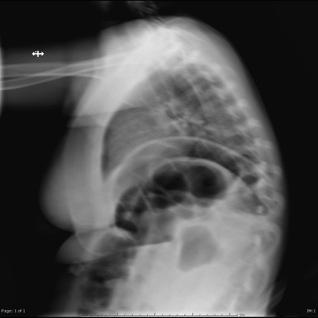

With the aim of producing high-quality X-rays with minimal radiation exposure, particularly in children, researchers have developed a new approach to imaging patients. Surprisingly, the new technology isn't a high-tech, high-dollar piece of machinery. Rather, it's based on the Xbox gaming system.

Using proprietary software developed for the Microsoft Kinect system, researchers at Washington University School of Medicine in St. Louis have adapted hands-free technology used for the popular Xbox system to aid radiographers when taking X-rays.

The software coupled with the Kinect system can measure thickness of body parts and check for motion, positioning and the X-ray field of view immediately before imaging, said Steven Don, MD, associate professor of radiology at the university's Mallinckrodt Institute of Radiology. Real-time monitoring alerts technologists to factors that could compromise image quality. For example, "movement during an X-ray requires retakes, thereby increasing radiation exposure," Don said.

The technology could benefit all patients but particularly children because of their sensitivity to radiation and greater variation in body sizes, which can range from premature infants to adult-sized teenagers. Setting appropriate X-ray techniques to minimize radiation exposure depends on the thickness of the body part being imaged. High-quality X-rays are critical in determining diagnoses and treatment plans.

"To achieve the best image quality while minimizing radiation exposure, X-ray technique needs to be based on body-part thickness," Don said. The gaming software has an infrared sensor to measure body-part thickness automatically without patient contact.